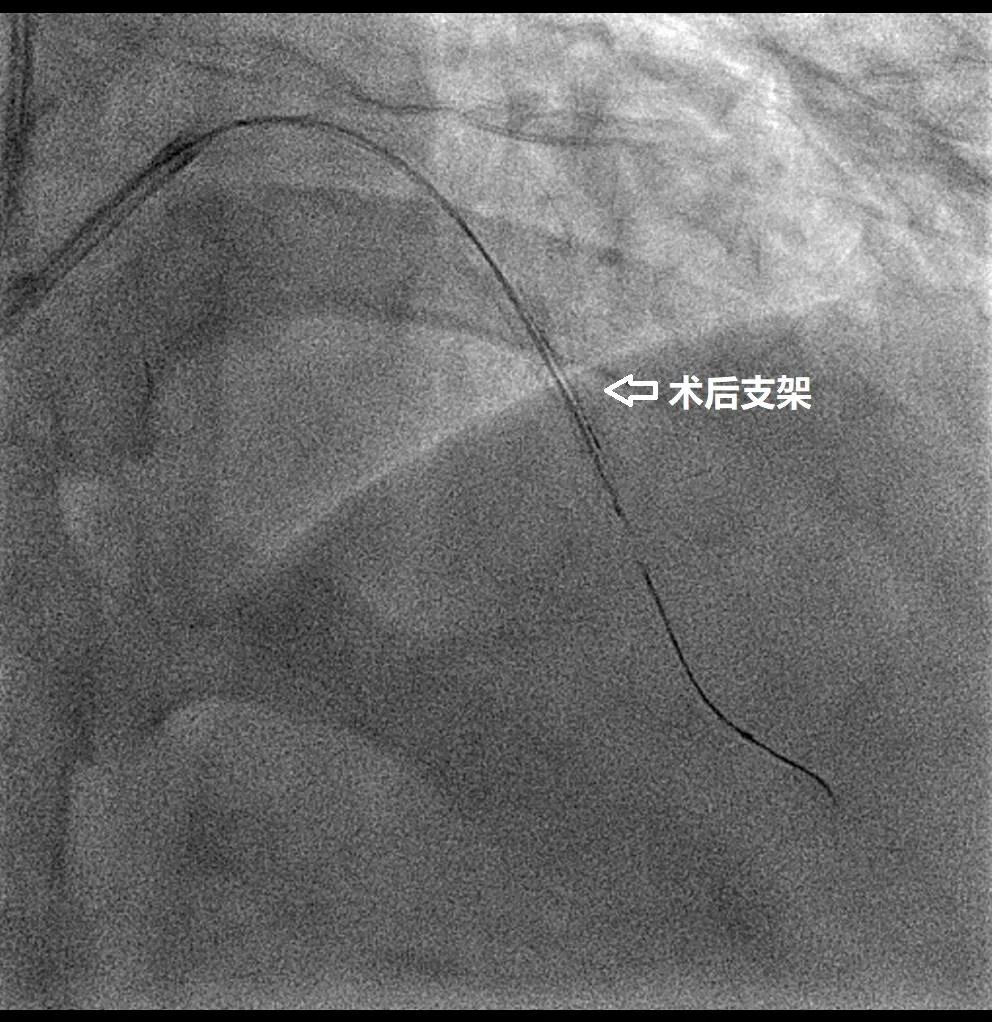

术后X线下支架显影。